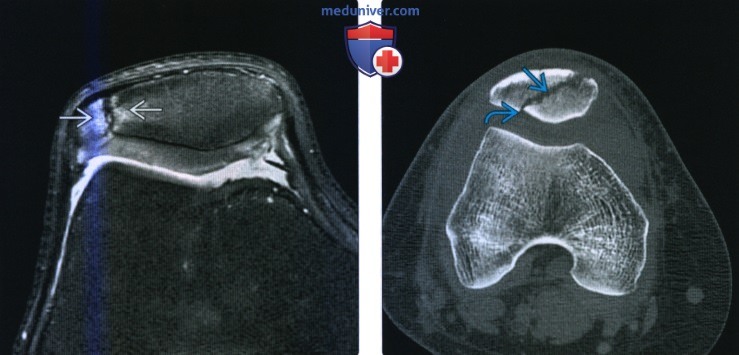

Как и при любой травме коленного сустава для постановки правильного диагноза выполняется рентгенография, на которой-то и можно увидеть перелом. Обычно рентгенографию выполняют в прямой и боковой проекциях, а для диагностики вертикальных переломов выполняют еще и осевую (аксиальную, или Merchant) проекцию.

Прямая (слева) и боковая (справа) проекции, на которых виден горизонтальный перелом надколенника со смещением отломков. Осевая проекция. Вертикальный перелом. Обратите внимание на возникшую в результате смещения ступеньку на скользящей поверхности надколенника.

Осевая проекция. Вертикальный перелом. Обратите внимание на возникшую в результате смещения ступеньку на скользящей поверхности надколенника.Иногда для более точного диагноза могут потребоваться компьютерная и/или магнитно-резонансная томография, но, в подавляющем большинстве случаев, достаточно рентгенографии.